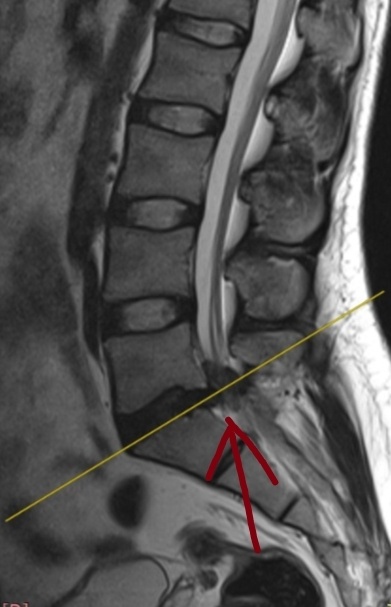

Попросили посмотреть, просто по знакомству. Парень, 29 лет, водитель.

Жалобы на боли в спине, отдают в правую ногу. Сейчас чуть лучше. На МРТ такая штука.

Здоровая протрузия и изменения в тканях.

Скорее всего перидурит (воспаление тканей вокруг корешков).